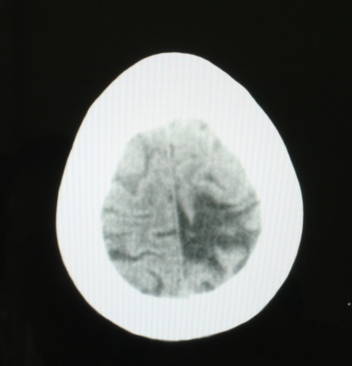

无占位效应,周围脑沟清楚,支持软化灶。

病灶周围有负压性改变,多为脑软化灶。

左顶叶局限性脑水肿,可以考虑增强看看,排除肉芽肿,比如脑血吸虫病等。

左顶叶不规则低密度灶后缘隐约见略高密度影,软化灶不能完全解释,建议增强检查或mai检查。